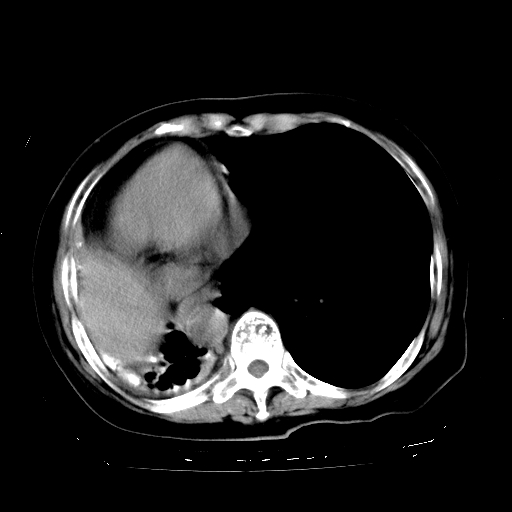

标题: CT23991:女,72岁,咳嗽、憋气一周。 [打印本页]

女,72岁,咳嗽、憋气一周,十年前曾患肺结核及胸膜结核。

1.右侧损毁肺伴胸膜钙化,2.左肺小结节灶,良性可能大,注意复查。3.肝脏左叶囊肿。4.先天性一侧肺不发育待出外(右侧胸廓无明显塌陷)。对比原片应该非常有帮助。

肝脏转移

支持楼上,肝脏多发囊肿